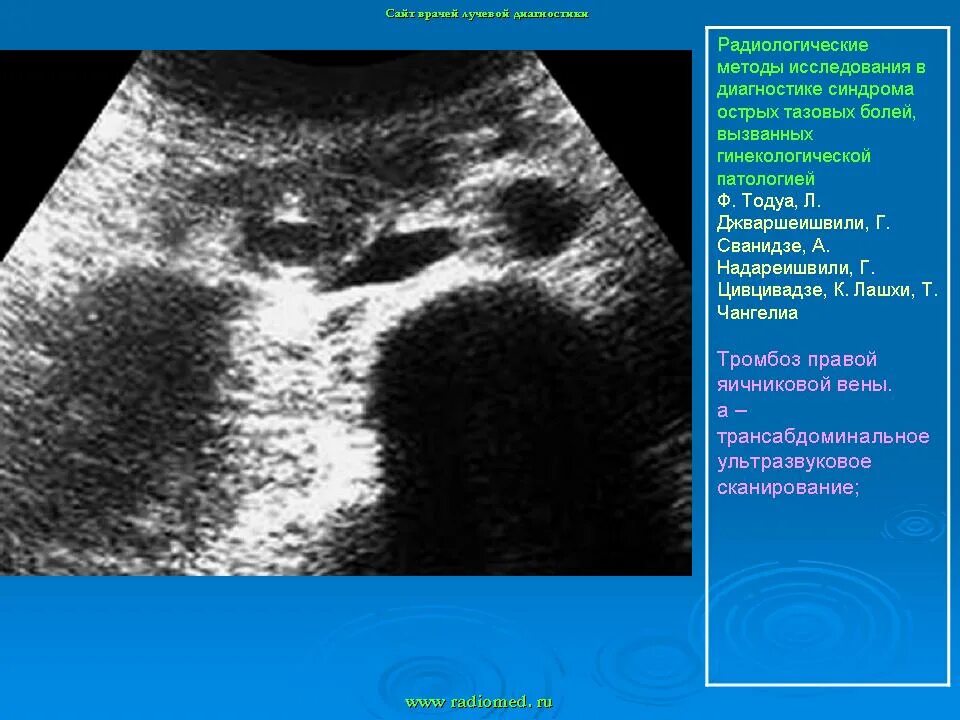

Узи аномалий